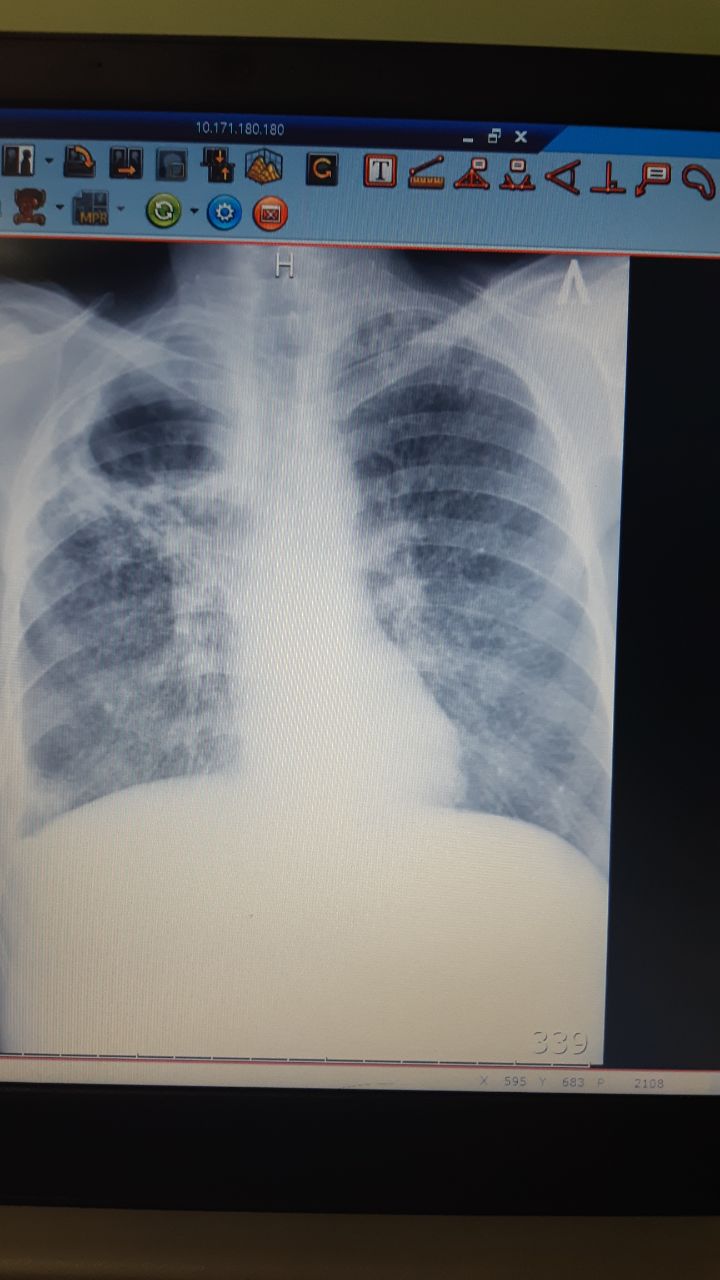

Здравствуйте,ваше мнение,анамнеза нету.

На фоне синдрома утечки воздуха оценить состояние легочных полей проблематично. Поэтому просто пишем что видим. Синдром утечки воздуха: двусторонний пневмоторакс, пневмомедиастинум, подкожная эмфизема. Контроль в динамике.